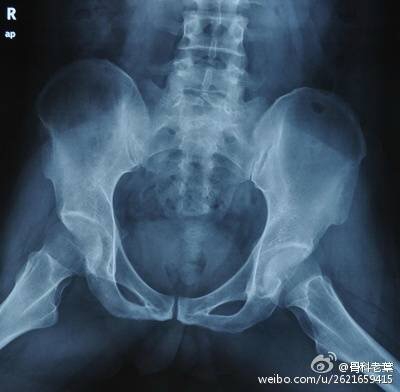

II期 病人有髋部症状,磁共振出现异常,X线片显示股骨头出现透光和硬化改变

III期 磁共振出现异常,X线片显示软骨下塌陷(新月征),股骨头内出现空洞,股骨头没有变扁

II期和III期的患者治疗方法相同,因为此时股骨头虽然还没有变形,暂时还不需要行人工关节置换术,但是股骨头已经出现空洞,随时股骨头就会塌陷变形,所以单纯的股骨头减压术是不能达到治疗效果的。这时就需要在股骨头减压的同时,植入一根支撑棒,顶住股骨头空洞区,防止股骨头在负重的情况下过早塌陷。其他治疗同之前相同,口服以上药物,定期复查,密切观察病情发展,尽量避免重体力劳动和爬山爬楼。